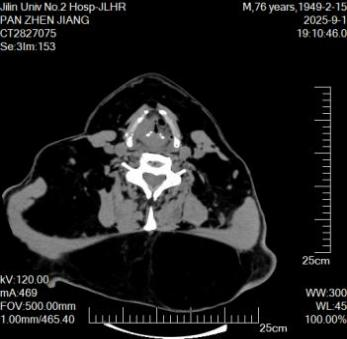

刘学识博杰介绍,该名患者颈前后区有巨大包块,直径约25cm,质地软,几乎完全覆盖颈前后区域。电子喉镜检查显示:双侧披裂固定,喉口狭窄。喉CT平扫证实:喉咽右侧壁、后壁软组织影增厚,右侧黎状窝变浅、消失,声门裂狭窄。